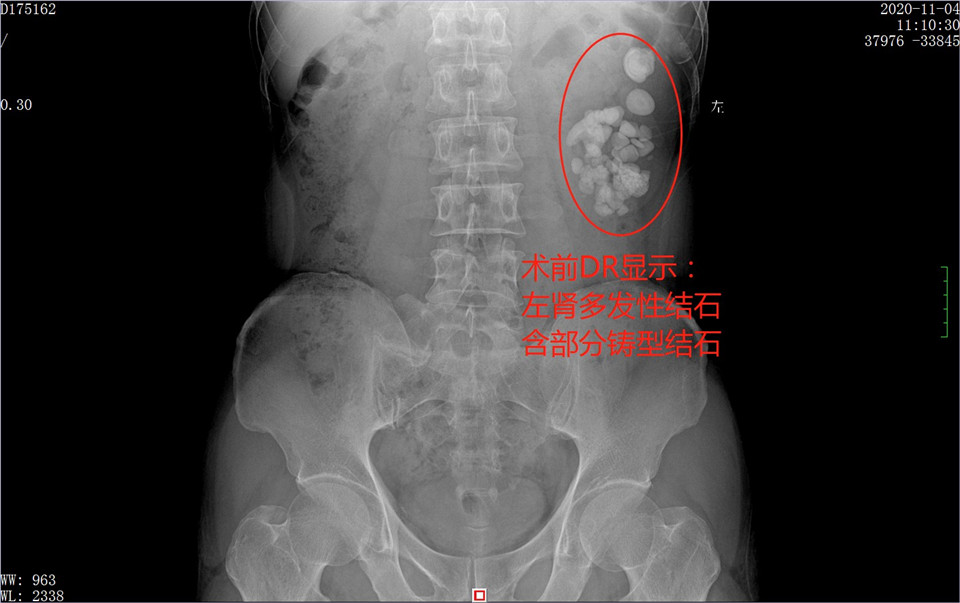

我们常说“防病大于治病,晚治不如早治”,这是我们对待疾病的基本态度和原则,然而,总有些人有病扛着、拖着,小病扛成大病,小威胁拖成大危害。让我们一起看看广西肾结石患者李某的“结石冒险记”。 险情一:20年前开始腰痛但不查不治 李某今年51岁,据他说大约20年前,也就是自己三十岁的时候开始感觉左侧腰痛的,当时痛感不是太强,过一阵也会不痛,然后又有时候会痛起来,就这样间断性的反复疼痛。自己当时在外地做工,经济上也不宽裕,所以能忍就忍了。当时自己想可能是干活的时候扭伤了或者是肾虚,总想着熬一下可能就好了。谁想到,忍了一年又一年,一熬就20年,从青年熬到中年,当初一个小结石熬成了多颗结石包含铸型结石。 外六科专家指出:肾脏是一个承担很大功能但特别不容易发出“危险信号”的器官,一般有病变也很难让人感知到疼痛或不舒服,因此对肾脏要格外关注。结石直接刺激肾脏让人感觉到疼痛,更应该积极治疗,有些结石也不会让人感觉到疼痛,悄无声息的长大、长多或者长成铸型结石。 因此,肾脏一旦有异常,切不可姑息,应该积极查明原因,尽早治疗。否则小结石只会变大、数量增多,到时候增加手术难度,且可能损害肾功能,严重者可能造成肾坏死、尿毒症,危及到生命。 险情二:肾积水伴多发性肾结石采取不当治疗 近期,李某由于感觉疼痛有加重趋势,加上年龄较大了,才开始重视身体健康了,于是没有继续忍受下去,选择前往医院治疗。但是没想到,当地就诊的医院采取体外碎石治疗,这给李先生又一次造成险情。因为以李先生目前的病情,属于多发性结石含铸型结石,且伴有肾积水,这是不适合体外碎石治疗的,不仅无效还有可能损伤肾脏,可谓雪上加霜。 外六科专家解释:体外碎石一般适合比较小的1cm左右及以下的单发性结石,对于较大的结石、多发性结石,以及结石引发肾积水的情况,是不适宜的。体外冲击波的能量小了,对结石没效果,能量太大了,又容易损伤肾脏,如果再碰到定位不准确的情况,那更是摧毁肾脏。因此,这个不当的治疗,也让李先生经历了一次险情。好在发现没效果后及时停止体外碎石,而选择来广州治疗。 险情三:今手术取石成功但肾功能受损严重 如今,李某来到广东药科大学广州复星禅诚医院外六科,得以最科学有效的治疗。专家组分析病情后,采取经皮肾镜+钬激光碎石取石微创手术,分两期进行,于2020年11月5日和9日两次手术,将填满肾脏的结石悉数击碎并取出,术后经复查,取石非常干净,一下解决了20年来的老毛病。手术虽然成功值得高兴,但是,李某的左肾却由于多年结石刺激,功能严重受损,又让人为之惋惜。 外六科专家强调:结石本就是小手术,随着医疗技术的不断进步,各种微创或无创的手术都广泛应用,可以轻松完成取石,手术时间仅1-2小时,术后恢复1-3天即可,完全没必要久拖不治。不治的结果,可不仅仅是结石长大了、长多了,而是对肾脏造成功能性损害,临床上见到的因结石导致肾功能损害、肾萎缩、坏死,引起尿毒症的病例屡见不鲜,令人痛心。李先生肾功能严重受损,好在没有完全丧失,差一点就废了这颗肾。